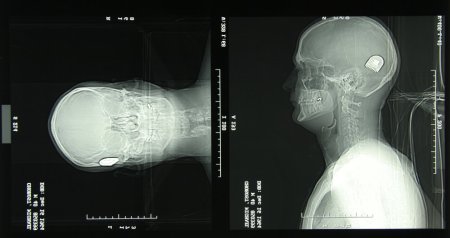

Interview with cochlear-implant user Michael Chorost and a leading cochlear implant surgeon

At the California Ear Institute, Michael Chorost talks with Joseph Roberson, the surgeon who gave Michael his implant.